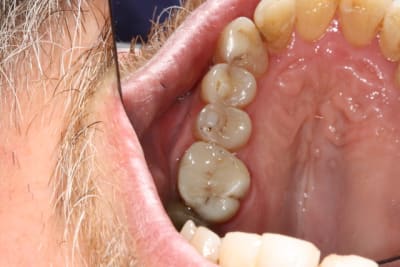

Photo 1. Moi: "Voilà pourquoi il vous faut un onlay."

Photo 3. Le patient: "Ah quand même! Ben on va faire les autres alors!"